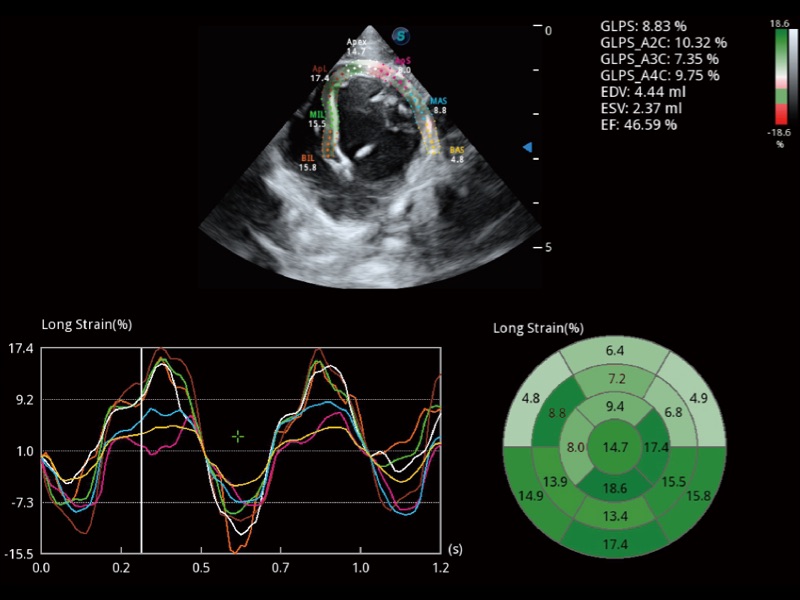

實(shí)時(shí)用顏色表示心肌組織運(yùn)動(dòng),觀察和定量組織的運(yùn)動(dòng)情況,對(duì)快速檢測(cè)與評(píng)估心肌的灌注和活性、電傳導(dǎo)及心肌收縮和舒張功能等均能提供重要的診斷信息。